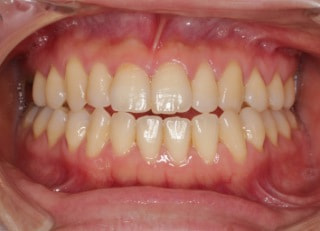

治療後(2年4ヶ月後)